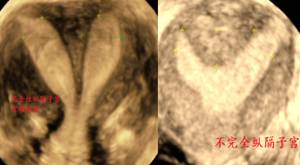

六、纵隔子宫

图:双角子宫与纵隔子宫鉴别

图:(左图)完全性子宫纵膈和(右图)不完全子宫纵膈

宫体轮廓无论二维扫查或三维成像均无异常。但由于其内膜腔被纵隔一分为二,二维超声横切时环形肌层切面上出现两团圆形的内膜回声,如猫眼一样,故称“猫眼征”。如为完全纵隔子宫,从宫底至宫颈管的横切面上始终呈现该猫眼征。如为不完全纵隔子宫,从宫底向下直至隔底水平,横切面上均呈现该猫眼征,而低于隔底水平的横切面上仅显示一团内膜。

三维超声上,完全纵隔子宫腔呈兔耳型,整个宫腔被纵隔完全分开。不完全纵隔子宫腔呈Y型,即隔底水平以下为一个宫腔。纵隔深度(两侧宫角的内膜顶点连线中点至纵隔底部的距离)≥10mm。

推荐使用ESHR的定义:宫底浆膜层内陷<子宫前后壁平均厚度50%且宫腔底部下凹深度>宫壁厚度50%,诊断为纵隔;若宫底浆膜层内陷>子宫前后壁平均厚度50%,为双角子宫。